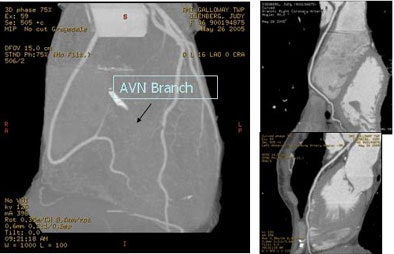

![]() |

| A 59-year-old man presented with classic chest pain symptoms to the ER five days earlier. He was asymptomatic upon presentation to the practice, but opted for an office-based CTA rather than wait three weeks to see a cardiologist. Images top to bottom: Right coronary artery stenosis (arrows) shown on 64-slice CTA at left, cardiac catheterization at right. Next, a normal left circumflex artery (arrows) is depicted on 64-slice CTA at left, cardiac catheterization at right. Next two image sets: Left anterior descending artery stenosis (arrows) is seen on 64-slice CTA at left, cardiac catheterization at right. Bottom image shows excellent outcome on cardiac cath following stenting. |